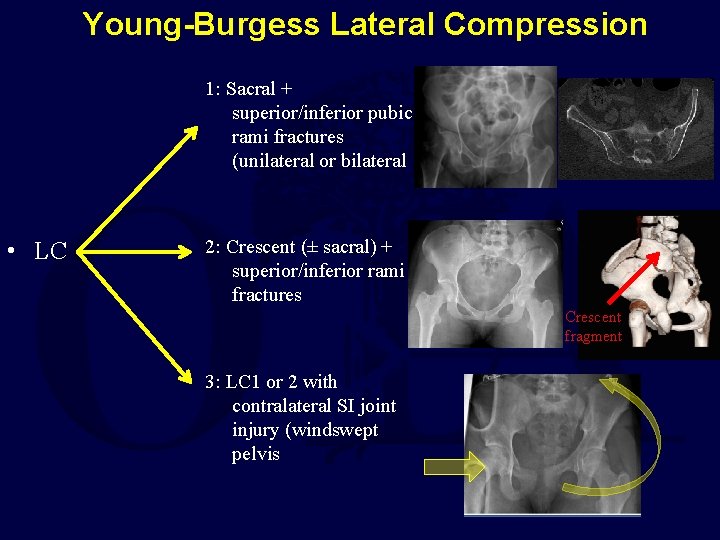

Young-Burgess Lateral Compression 1: Sacral + superior/inferior pubic rami fractures (unilateral or bilateral • LC 2: Crescent (± sacral) + superior/inferior rami fractures Crescent fragment 3: LC 1 or 2 with contralateral SI joint injury (windswept pelvis